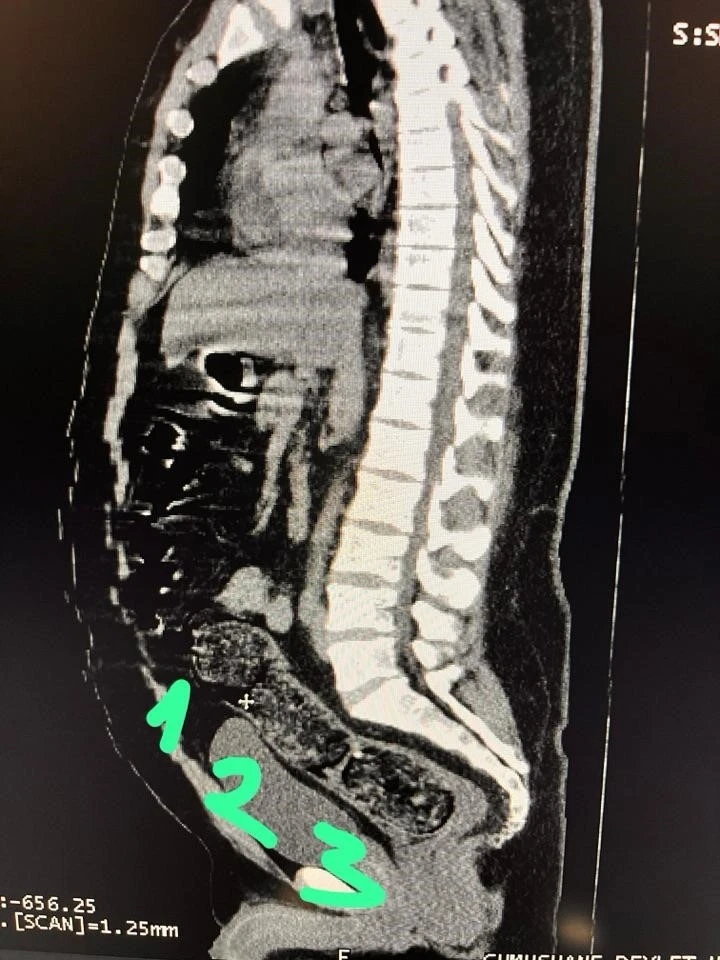

Adli makamların talimatı üzerine Gümüşhane Devlet Hastanesine götürülen şahsa yönelik iç beden muayenesinde bağırsaklarında 3 adet kapsül olduğu tespit edildi. Hastanede yapılan müdahalenin ardından şahsın bağırsaklarından çıkarılan kapsüllerin içerisinde toplamda 271,55 gram metamfetamin ele geçirildi.